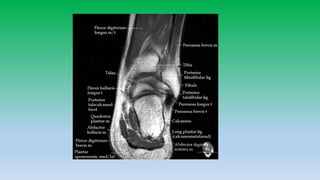

Posterior ankle tendons:

• Achilles and plantaris tendons are located in midline of posterior ankle and is

largest tendon in the body, diffusely low in signal intensity. Usually has flat or

concave anterior margin on axial images. Becomes convex when diffusely

thickened. Normally tendon measures 7 mm in AP-diameter.

• Does not have tendon sheath so cannot have tenosynovitis, but have paratenon

so Para-tendinitis can occurs. Paratenon is seen as thin line of intermediate signal

intensity on axial images.

• Plantaris lies anteromedial to Achilles tendon with high signal intensity fat plane

between.

• Tear of Achilles tendon occurs 4cm above the calcaneus insertion or at

musculotendinous junction.

• Retro-calcaneal bursa is located b/w the tendon and posterior aspect of

calcaneous, whereas tendoachilles bursa is located posterior to tendon in

subcutaneous fat.

Lateral ankle tendon:

• Peroneus brevis and peroneus longus tendons pass posterior and

inferior to lateral malleolus in the retro-malleolar groove.

• Peroneus brevis is flatter and broader lies anterior to longus, whereas

peroneus longus is posteriolateral and is more rounded. Peroneal

tendons are held inplace by superior retinaculum.

• Split tears are common in brevis.

• Peroneal tendons can sublux or dislocate , whenever there is tear of

superior retinaculum. Diagnosis is made if tendons are located lateral

to distal fibula rather than posterior to it. Hypoplastic retromalleolar

groove can predispose to subluxation.